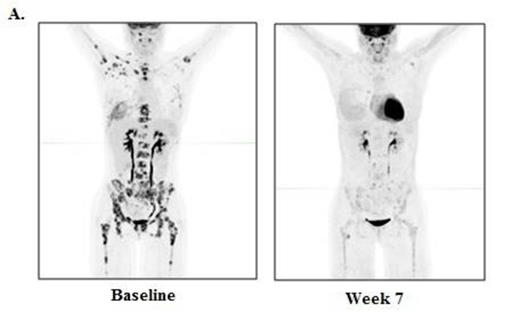

RESULTS: Thirteen patients were enrolled, with 6 patients at dose level 1 (3 mg/kg) and 7 patients in dose level 2 (10 mg/kg). The median age at time of transplant was 52 (range 20-70), and the median time from allo-HCT to study enrollment was 19.3 months (range 6.2 - 49.3). The median number of prior therapies was 7 (range 2-11), and 9 patients had received prior therapy for their post transplant relapse, including 4 patients with prior DLI. Seven patients had related donors and 6 patients had unrelated donors. Histologies included cHL (n=4), NHL (n=3), AML (n=2), and 1 patient each had MM, MDS, MPN, and ALL. In the safety analysis, there was no acute GVHD and one case of chronic GVHD (liver, mild) at 3 mg/kg, which was the only DLT. Immune-related adverse events (irAEs) were observed in 2 patients, and included grade 3 thrombocytopenia due to ITP (n=1), grade 2 pneumonitis (n=2), and grade 2 diarrhea (n=1), all of which were rapidly reversible with steroids and did not preclude further ipilimumab dosing. Eight patients discontinued due to progressive disease, 1 patient due to cGVHD, and 4 patients remain on treatment. The MTD was not reached. In the preliminary efficacy analysis, 4/11 (36.4%) patients evaluable for response had clinical benefit, including 1 cHL patient with a formal response, and 3 patients with stable disease with evidence of anti-tumor activity. The cHL patient achieving PR had a dramatic reduction in nodal and extranodal disease (Figure 1A), with a complete marrow response at 7 weeks (baseline 90% involement) (Figure 1B). A second cHL patient had a substantial reduction in disease burden and remains on study > 7 months, after progressing through 11 prior lines of therapy. A patient with CTCL also continues on study with stable disease > 6 months. A patient with AML/myeloid sarcoma had a tumor flare at 7 weeks followed by a reduction in tumor size at 13 weeks. The median follow-up time among survivors is 6.2 months, and 6 month overall survival is currently 65%. Immunophenotyping studies revealed that the ratio of regulatory T cells to conventional T cells decreased between 24% and 41% after ipilimumab treatment.

Baseline and week 7 re-staging studies in a classical Hodgkin lymphoma patient after 2 doses of ipilimumab at 10 mg/kg. A. PET/CT scan and B. Bone marrow (CD30 stain)